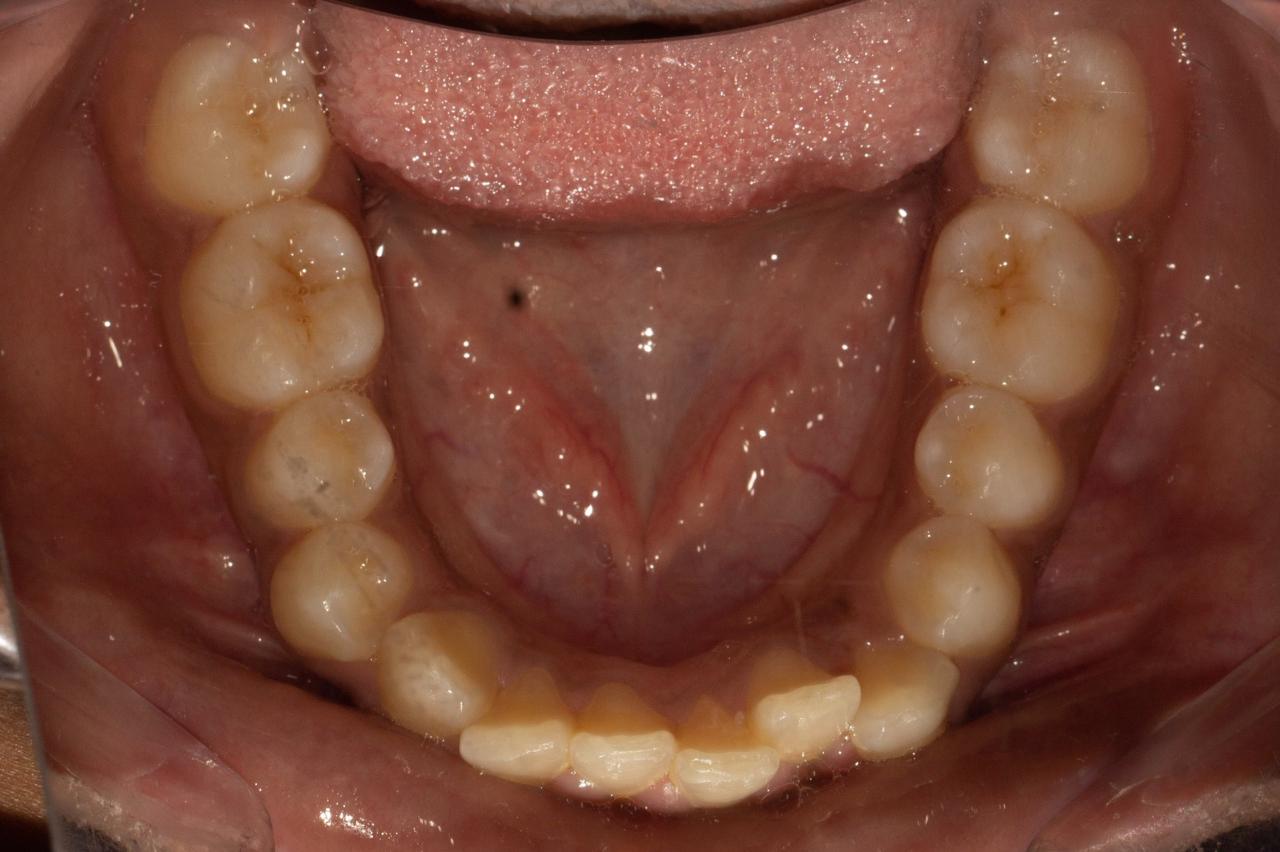

Fix misaligned teeth with braces or aligners through expert orthodontic treatment in Baner, Pune.